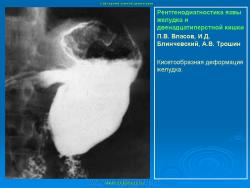

Пищеварительная система. Рентгенодиагностика язвы желудка и 12-ти перстной кишки. +

Рентгенодиагностика язвы желудка и 12-ти перстной кишки.